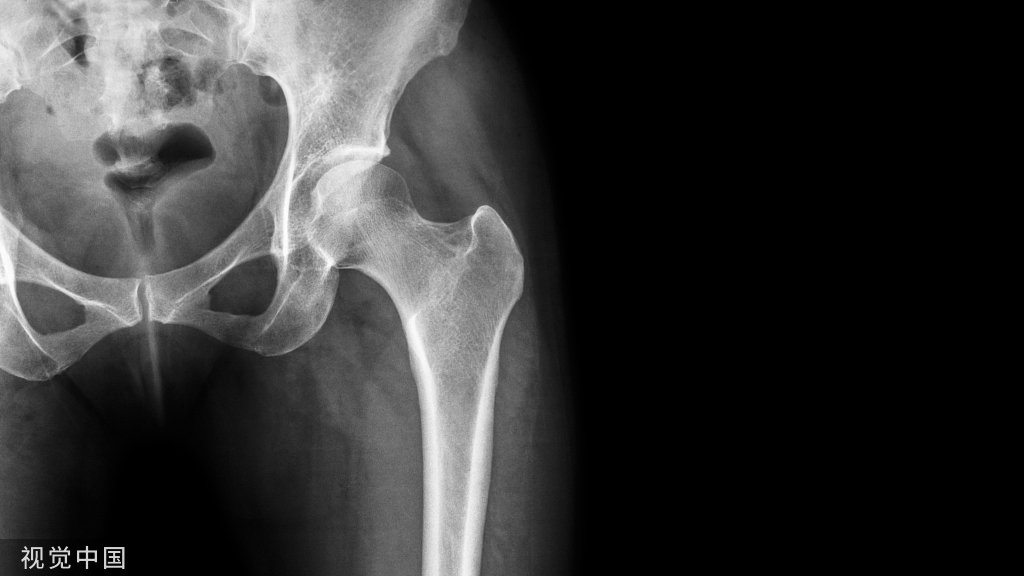

局部疼痛常见,压痛叩击痛常阳性,部分患者存在体位变化时疼痛,与骨质疏松性胸腰椎骨折相似。骶骨衰竭骨折常见于骶骨翼。X线和CT不易诊断,MRI和骨扫描是推荐的影像学检查,敏感度接近100%。成像特点和骨质疏松性胸腰椎压缩骨折类似,MRI T1低信号,T2和脂肪抑制像呈片状高信号。如下图所示,骶骨MRI显示双侧骶骨翼冠状图像上信号增加,表明双侧骶骨翼骨折引起明显的骶骨水肿。